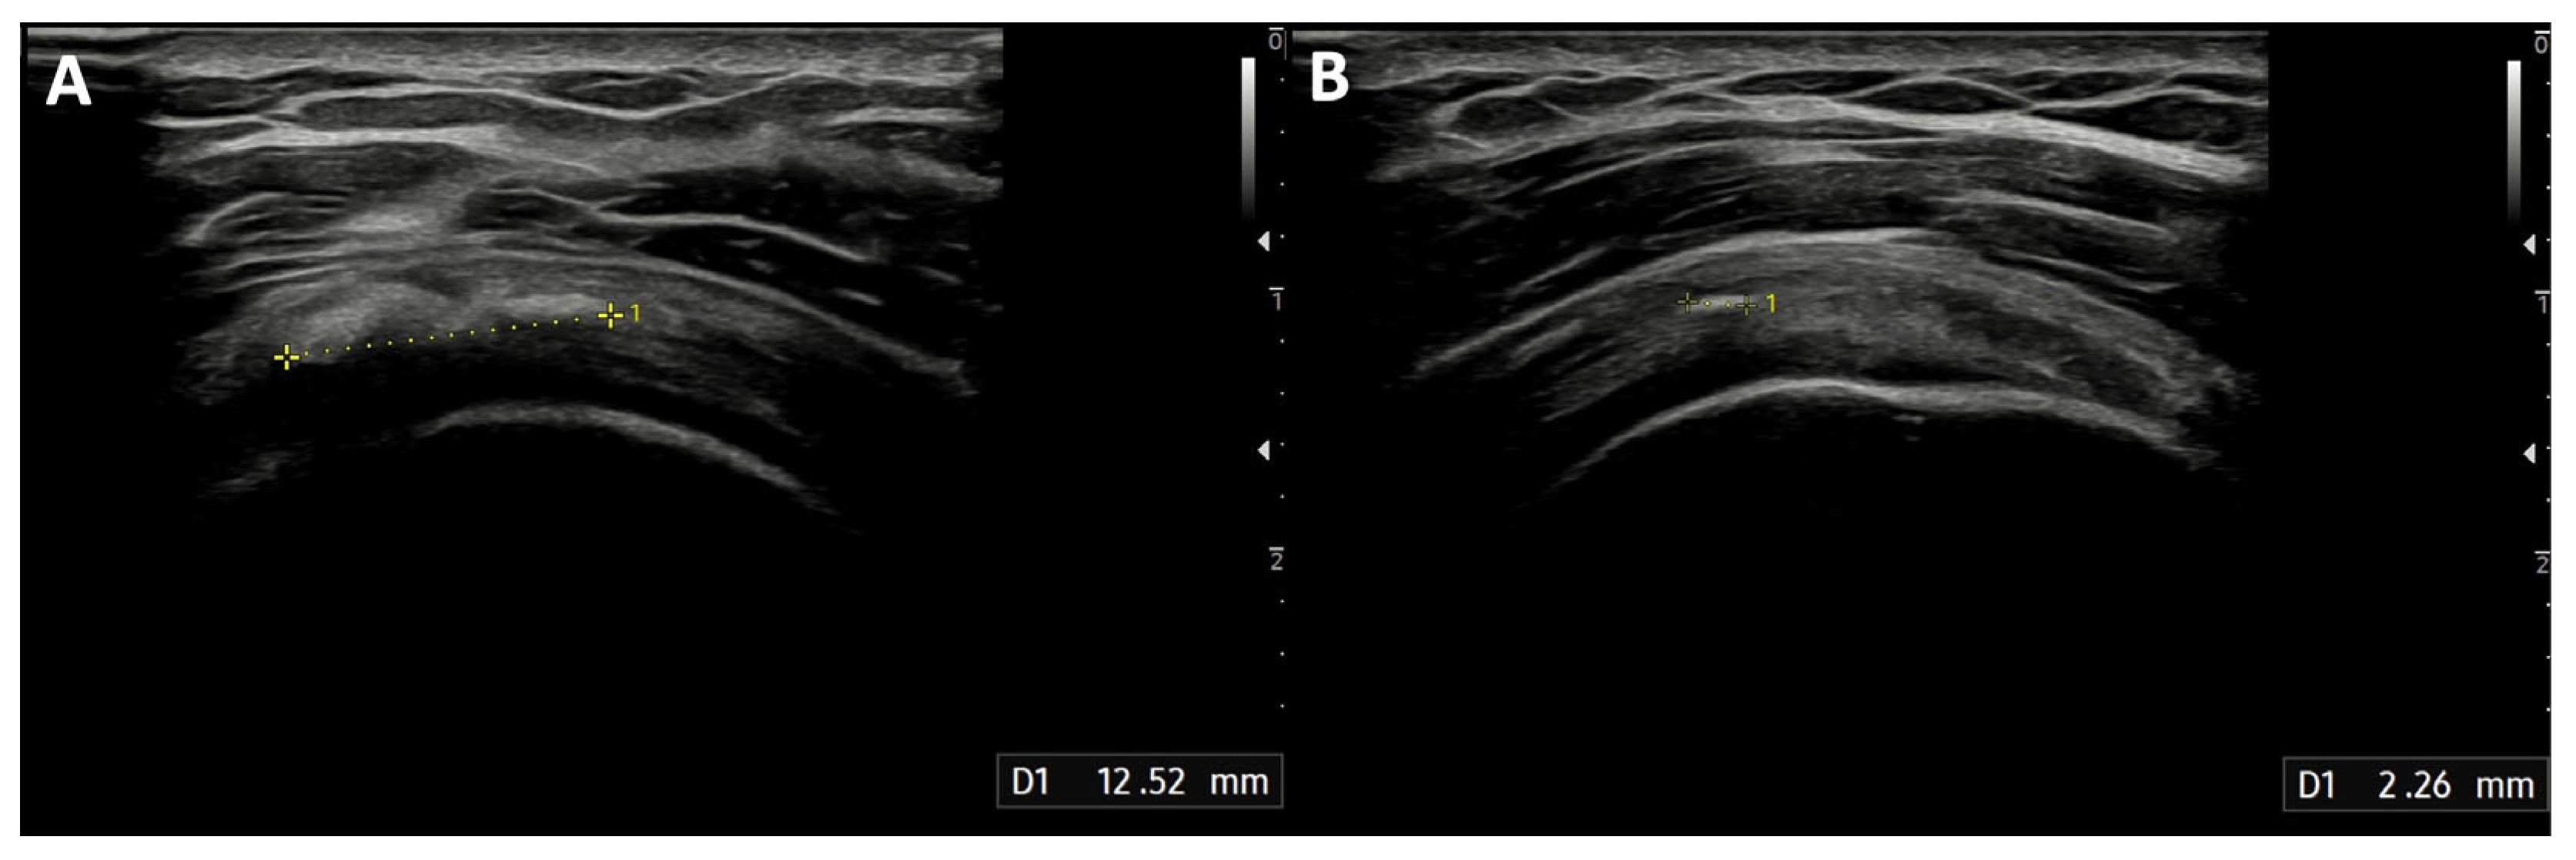

The median diameter of the calcification before the treatment was 12 mm (IQR: 10–20 mm). After the procedure, the calcification dimensions reduced significantly (Figure 4), with a median of 5.5 mm (IQR: 2–10 mm; p < 0.001), and 41 min (IQR: 39–45 min) was the median duration of the treatment. None of the patients experienced infections after the procedure. Two patients developed post-procedural bursitis, diagnosed with clinical and US examination 1 month after the procedure, which was easily resolved with a 4 mL injection of 2% lidocaine solution and steroids into the SASD bursa.

Figure 4. Reduction in supraspinatus tendon calcification treated with the ultrasound-guided closed-circuit irrigation procedure: (A) Ultrasound scan showing calcification of the supraspinatus tendon before the procedure, measuring 12.52 mm; thus, the patient was included in the study and underwent the closed-circuit double-needle irrigation technique. (B) Ultrasound image showing the same calcification 3 months after the procedure, with a significant reduction to a maximum diameter of 2.26 mm.